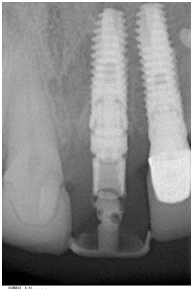

В качестве опоры был выбран конический имплантат XiVe.

Зуб 2.1 удалили без отслоения слизисто-надкостничного лоскута и выполнили препарирование ложа имплантата.

Установили конический имплантат с помощью хирургического шаблона с одномоментной костной аугментацией с применением остеокондуктивного материала Bio-Oss и барьерной мембраны Bio-Gide.

Контрольный постоперационный снимок показал удовлетворительное соединение имплантата с костной тканью лунки.

Первичная стабильность имплантата позволила установить временную реставрацию (коронку) с винтовой фиксацией.

С целью минимизирования окклюзионной и боковой нагрузки на имплантат режущий край коронки оставили на 1-1,5 мм короче, чем у соседних зубов.